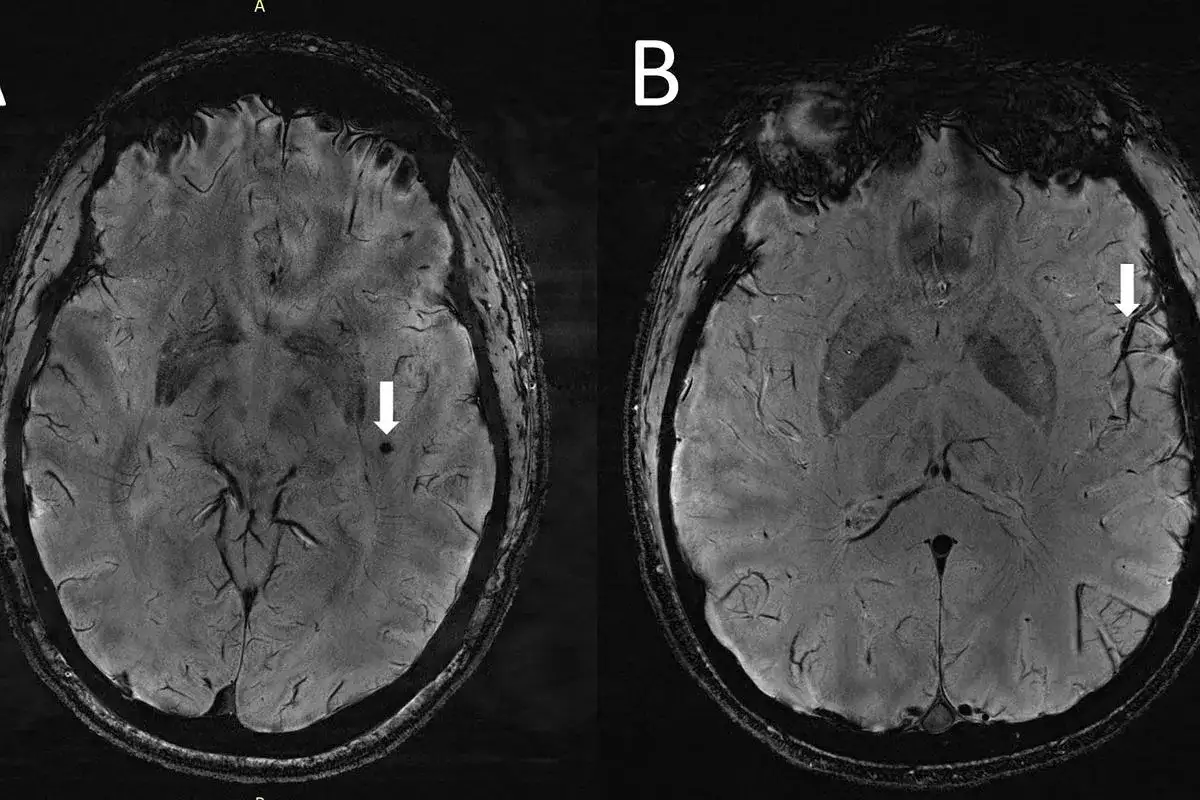

Dowiedz się, czy rezonans magnetyczny głowy wykryje choroby psychiczne. Rozwiewamy mity o roli MRI w diagnozie nerwic, ADHD i jego znaczeniu w psychiatrii. Sprawdź!